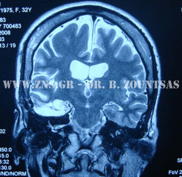

ΑΜΥΓΔΑΛΟΪΠΠΟΚΑΜΠΕΚΤΟΜΗ αριστερά